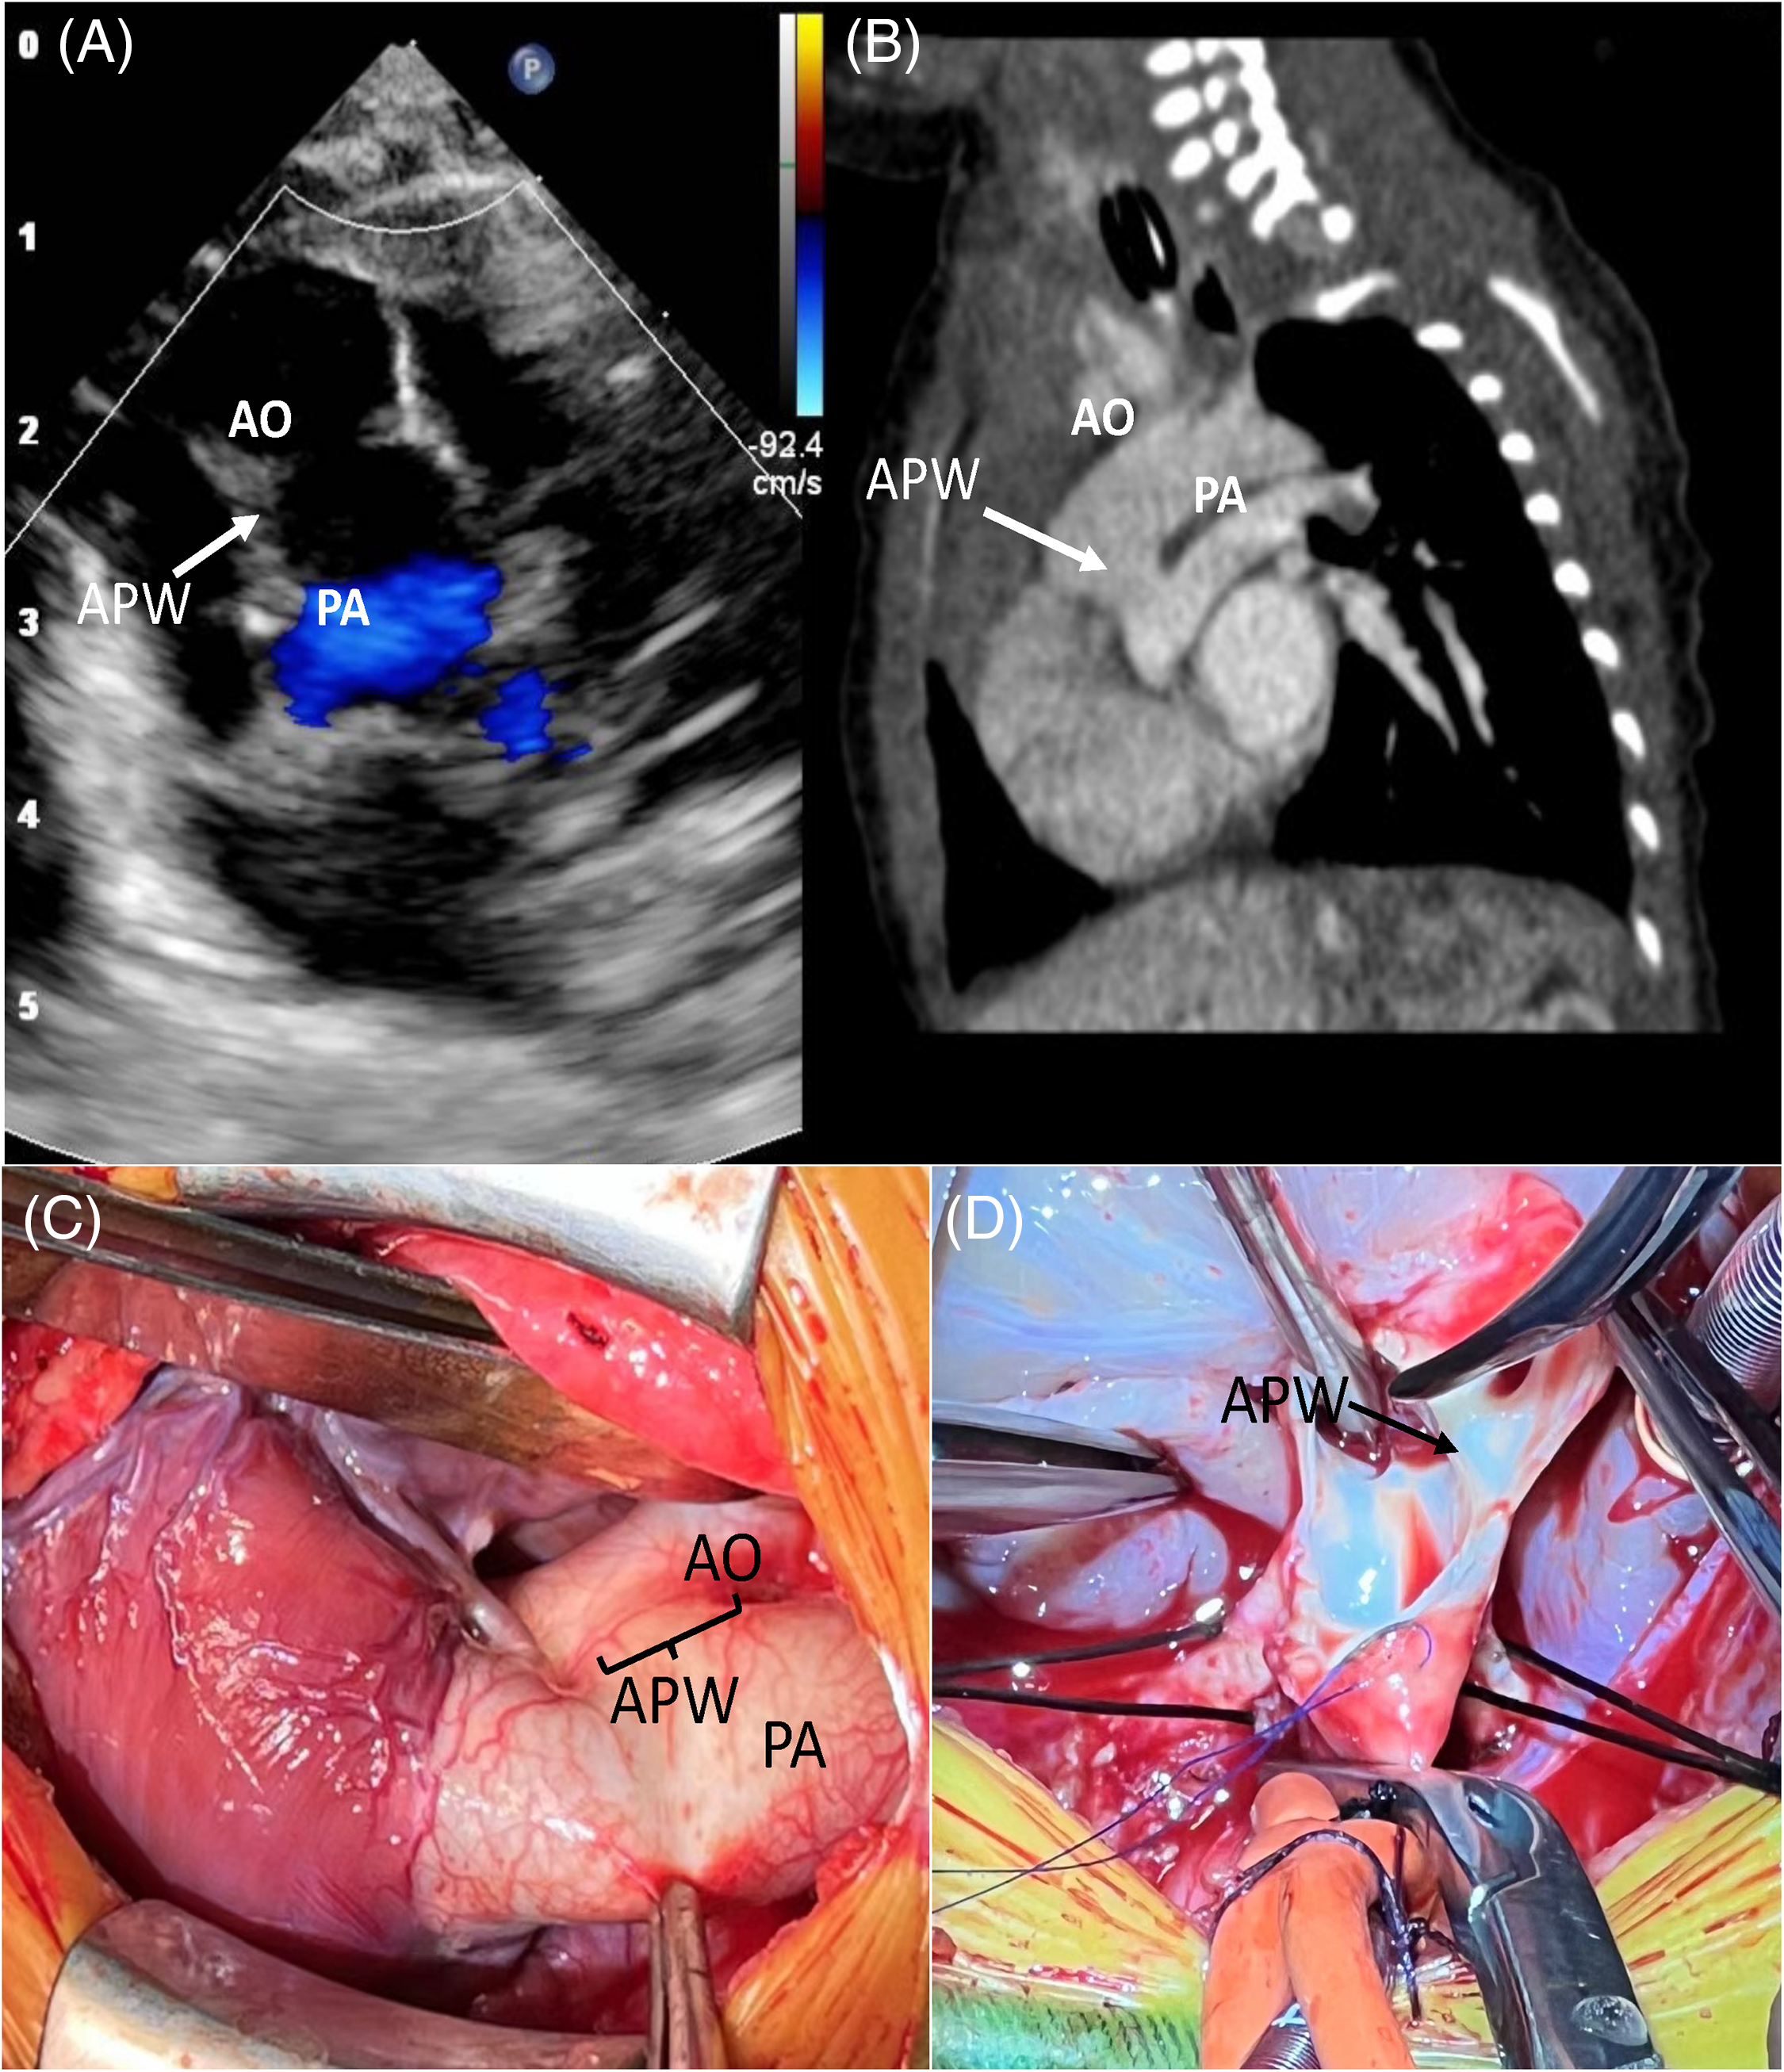

A term male newborn with a birth weight of 3 kg was transferred to our cardiac center due to hypoxia and heart murmur 1 day after birth. Echocardiography in our institution showed dextro-TGA/IVS with APW (type I) and no patent ductus arteriosus (PDA) was found (Fig. 1). Preoperative cardiac computed tomography (CT) proved the diagnosis and showed APW 7 mm above the pulmonary valve. The CT also showed coronary artery anatomy 1 LAD, Cx, and 2 RCA according to the Leiden classification. An elective arterial switch operation (ASO) was performed at 25 days with a body weight of 3.8 kg.

Figure 1: Preoperative echocardiography (A), computed tomography (CT) (B), and direct view (C, D) of this case. AO: Aorta, PA: Pulmonary artery; APW: Aortopulmonary window

We first inspected the anatomy of the coronary arteries and it turned out to be coherent with the CT scan. The APW was divided, and the main pulmonary artery and the aorta were transected at the distal side of the APW after routine cardiopulmonary bypass. The size of the APW was around 10 mm and the proximal anterior wall of the neoaorta was only 6–7 mm. After two coronary artery buttons were excised and anastomosed, we mobilized the branch pulmonary arteries to the hilum, and the LeCompte maneuver was performed. The distal end of the ascending aorta was then anastomosed directly to the pulmonary root, followed by right atriotomy and closure of patent foramen ovale. The neopulmonary was then reconstructed with an autologous pericardium patch. The heart recovered well after removing the aorta cross-clamp while the left ventricle became distended when decreasing the flow rate. The cardiopulmonary bypass time was 200 min and the aorta cross-clamp time was 122 min. Extracorporeal membrane oxygenation (ECMO) was finally applied after the surgery and weaned off 6 days after the ASO. Tracheal intubation was removed 2 days later and discharged 12 days later. The patient was followed up for 4 months and is growing well.